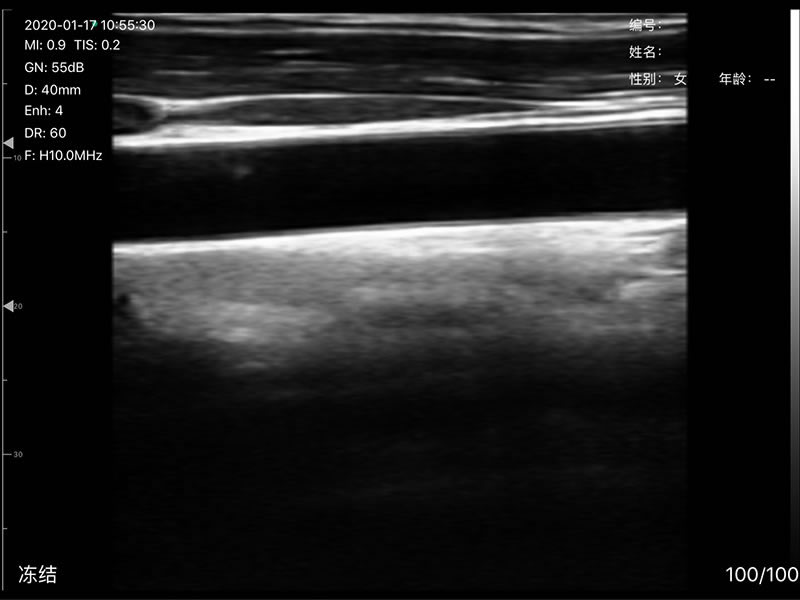

• 探头频率:相控阵2.2/3.6MHz,线阵7.5/10 MHz

• 扫描声头:同时具备微凸、线阵两个声头,并可通过按键快速切换

• 扫描深度:相控阵20-240mm,线阵 20-100mm,可调

• 扫描角度和宽度:相控阵80mm,线阵25mm